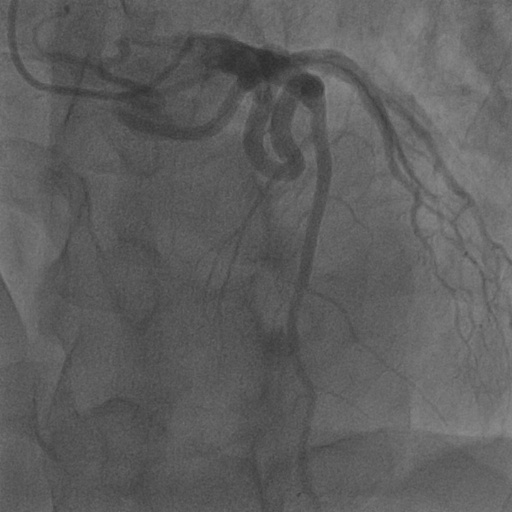

Since supervised training and testing data are from the same dataset (in-domain setting), its performance will be better than that of self-supervised or unsupervised methods. However, it is worth noting that in this scenario, our method does not require any labels and can still outperform existing self-supervised methods. Also, we test the CADICA dataset to compare the generalization ability of supervised training and our proposed unsupervised training in Figure 8. We find that supervised methods are limited by the domain of their training data and thus struggle to generalize well. Our method, while requiring test-time training, can adapt to various datasets in an unsupervised manner. This allows for greater flexibility and generalization across different types of vascular video data.

We calculate the AUROC and AUPRC in Figure 6. We normalize the model’s final layer output to [0, 1] to use it as the probability for calculating AUROC and AUPRC. Our model performs favorably against other methods on both AUROC and AUPRC. We also provide visual comparison results in Figure 7, demonstrating our vessel segmentation results are more accurate, complete, and closer to the ground truth masks. Moreover, in some sequences, our method even performs on par with supervised U-Net (Ronneberger et al., 2015), as U-Net might face an overfitting problem with insufficient training data. Additionally, we provide visual comparisons on the CADICA (Jiménez-Partinen et al., 2024) dataset, which is also a coronary artery X-ray video dataset but without ground truth labeling. Figure 8 demonstrates that our test-time training scheme generalizes better than existing methods. Due to the space limit, we provide more visual comparisons in the appendix.